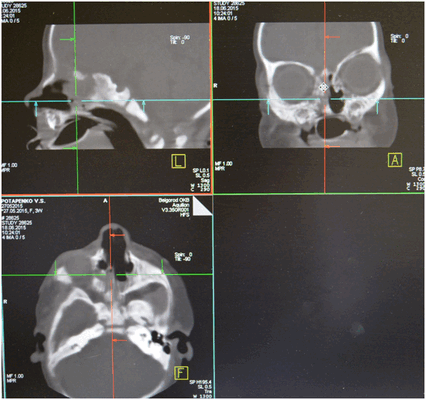

Для диагностики атрезии хоан используют разные методы: зондирование полости носа, рентгендиагностика с контрастным веществом. В настоящее время широкое применение получила компьютерная томография придаточных пазух носа. Двусторонние полные или частичные атрезии диагностируют у новорожденных и у детей раннего возраста. Односторонние частичные же атрезии хоан могут быть диагностированы и в более позднем возрасте, связано это с тем, что при таких атрезиях носовое дыхание лишь затруднено, а с одной стороны и вовсе не нарушено.

Из анамнеза известно, что указанные жалобы беспокоят с рождения. Ребенок родился в срок 40-41 неделя (27.05.2015), на фоне нарастания дыхательной недостаточности, через два часа после родов проведена интубация трахеи. Экстубация трахеи - 29.05.2015. С 01.06.2015 по 20.06.2015 с диагнозом нижнедолевая сегментарная правосторонняя пневмония, пиодермия, ринит, конъюнктивит девочка была на стационарном лечении в ОГБУЗ "Детской областной клинической больницы" г. Белгород. Проведено СКТ: картина двусторонней атрезии хоан. Рекомендовано консультация в НКЦО г. Москва. Ребёнок консультирован проф. Юнусову А.С. 22.06.2015 г. и направлен на хирургическое лечение в Отдел детской ЛОР патологии ФГБУ НКЦО ФМБА России.